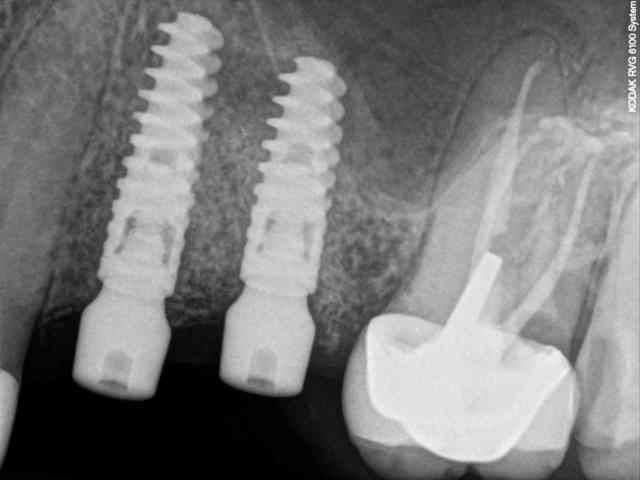

voici le dernier né de la gamme Axiom d'Anthogyr.

il est commercialisé depuis le premier janvier de cette année sauf pour ceux qui ont effectué les essaies cliniques (j'en faisais pas partie--snif!), ceux là pouvaient le commander avant.

les plus:

il a un corps conique et des spires beaucoup plus agressives pour augmenter la stabilité primaire.

son diamètre au niveau du col est légèrement réduit ce qui limite la compression crestal.

on conserve exactement la même connectique que son grand frère l'Axiom REG donc aucun changement pour la prothèse et bien entendu on conserve aussi le platform switching.

le moins:

à éviter sur les os de type D1

le cas que je vous présente date d'hier, il n'a rien d'extraordinaire, alors soyez indulgents, c'était juste pour le plaisir de partager ça avec vous.

7-8-9-10-11- les radios

l’intérêt est surtout lié à la stabilité primaire puisque c'est un implant plus spécifiquement dédié aux MCI.

ici, tu l'as compris, ce n'est pas vraiment nécessaire excepté pour la 2 ième prémolaire où l'extraction est très récente (2 mois à peine) et où l'alvéole à été comblée par un biomatériaux.